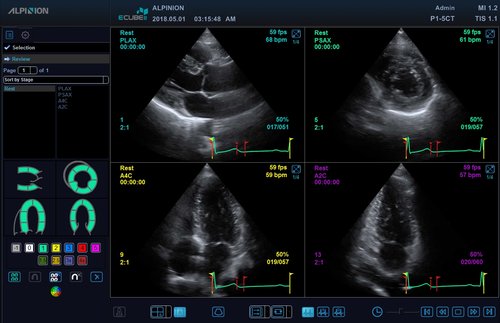

• M-Modus, Auto IMT, CV Measurement and Report, EKG, Cube Strain, Stressecho, Tissue Doppler Imaging (Kardiologie)

• P1-5CT (1-5 MHz) für Ultraschalluntersuchungen in Bereichen Kardiologie, Abdomen, transkraniell

• SP3-8T (3-8 MHz) für Ultraschalluntersuchungen in Bereichen Kardiologie, Abdomen, transkraniell